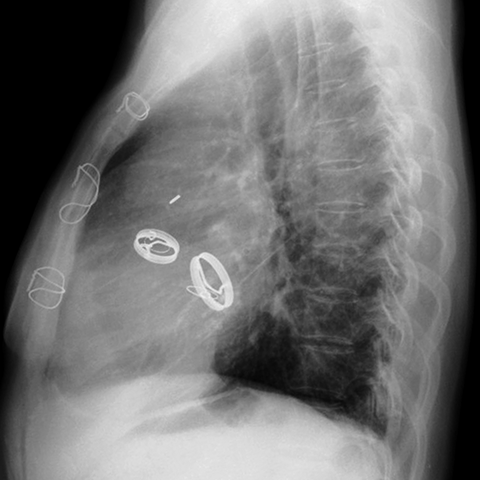

Prosthetic Aortic & Mitral Valves (Lateral CXR) [5 of 5]